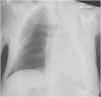

The X ray revealed an opacified white left lung (Fig. 1). Chest tomography scan showed the left airways filled with mucoid material, with atelectasis of the entire left lung and mediastinal shift to the ipsilateral side. Evaluation of the pulmonary parenchyma did not show any suspicious alterations, including consolidations or expansive lesions.